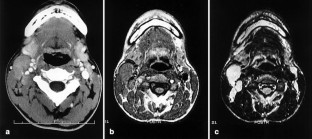

Syphilis is well known as a great mimic, however it is not recognized as a cause of cervical lymphadenopathy. We report a case of a 21-year-old man who presented with marked unilateral cervical lymphadenopathy. He had no evidence of oropharyngeal chancres, skin or genital lesions. Computed tomography (CT) and magnetic resonance (MR) images showed multiple cervical lymphadenopathy, and serologic tests for syphilis were positive. Syphilis should still be a factor for consideration in the differential diagnosis of cervical lymphadenopathy.

Fig. 1.

Fig. 2.